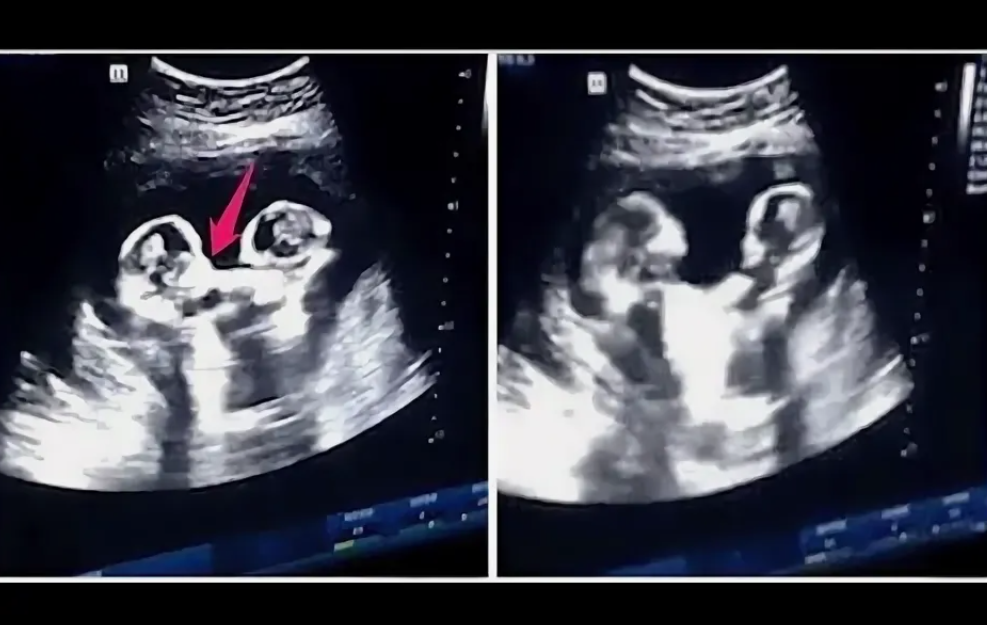

Она в свои 36 лет понимала, что шансы забеременеть с каждым годом все меньше и меньше. А тут вдруг двойня! Врач, делавший УЗИ, странно поглядывал на будущую маму, не решаясь высказать свое предположение. Но это необходимо было сделать, чтобы у матери было время подумать, оставлять беременность или прервать ее… Потому что в утробе были сиамские близнецы.

УЗИ с близнецами. Фото из интернета

Через месяц Ханна сделала еще одно обследования, на котором подтвердилось, что близнецы срослись. Ханна и Дэн точно ждали сиамских близнецов. Но супруги не унывали, говоря, что им подарил такое счастье Бог. В душе, конечно, оба переживали…

Потому что обследование показало, как именно срослись близнецы: у них были раздельные органы, два сердца, но сросшийся таз с четырьмя ножками, две из которых были недоразвитые.

Такой тип сращения называется монохорионический моноамниотик – у них кроме общей плаценты общий амниотический мешок. Из-за чего у них более высокая вероятность осложнений, начиная от выкидыша или преждевременных родов до аномалий в развитии плода или мертворождения.